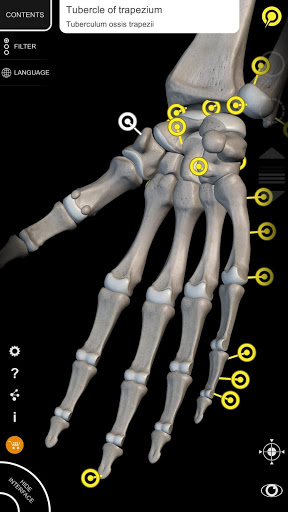

"Anatomy 3D Atlas" memungkinkan Anda mempelajari anatomi manusia dengan cara yang mudah dan interaktif.

Melalui antarmuka yang sederhana dan intuitif, Anda dapat mengamati setiap struktur anatomi dari sudut mana pun.

Model 3D anatomi sangat terperinci dan memiliki tekstur hingga resolusi 4k.

Pembagian berdasarkan wilayah dan tampilan yang telah ditetapkan sebelumnya memudahkan pengamatan dan studi bagian tunggal atau kelompok sistem dan hubungan antara organ yang berbeda.

saraf • Sistem pernapasan • Sistem pencernaan • Sistem urogenital (pria dan wanita) • Sistem endokrin • Sistem limfatik • Sistem mata dan telinga FITUR • Antarmuka yang sederhana dan intuitif • Putar dan perbesar setiap model dalam ruang 3D • Opsi untuk menyembunyikan atau mengisolasi satu atau beberapa model yang dipilih • Filter untuk menyembunyikan atau menampilkan setiap sistem • Fungsi pencarian untuk menemukan setiap bagian anatomi dengan mudah • Fungsi penanda untuk menyimpan tampilan khusus • Rotasi cerdas yang menggerakkan pusat rotasi secara otomatis • Fungsi transparansi • Visualisasi otot melalui tingkat lapisan dari yang superfisial hingga yang terdalam • Dengan memilih model atau pin, istilah anatomi terkait akan muncul • Deskripsi otot: asal, • Tampilkan/ Sembunyikan antarmuka UI (sangat berguna dengan layar kecil) MULTIBAHASA • Istilah anatomi dan antarmuka pengguna tersedia dalam 11 bahasa: Latin, Inggris, Prancis, Jerman, Italia, Portugis, Turki, Rusia, Spanyol, Mandarin, Jepang, dan Korea • Istilah anatomi dapat ditampilkan dalam dua bahasa secara bersamaan PERSYARATAN SISTEM • Android 8.0 atau yang lebih baru, perangkat dengan RAM minimal 3GB Reversi